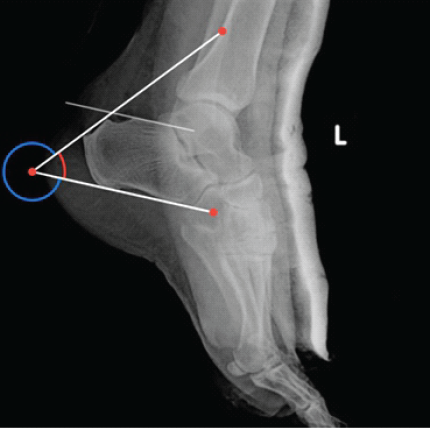

Giant Ganglion Cyst of the Tibialis Anterior Tendon Presenting with Adult-Acquired Flatfoot Deformity: A Case Report

Suraj Sajeev , Amit Bhardwaj ………………………………p.136-140